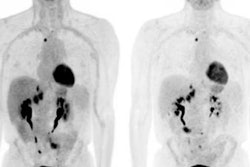

Indeterminate lesion on PET/CT classified by PET/MRI for 53-year-old man with lung cancer. Contrast-enhanced CT (A), PET (B), and fused F-18 FDG PET/CT (C) images are displayed in comparison with contrast-enhanced T1-weighted MRI (D), PET (E), and fused F-18 FDG PET/MRI (F) images. In CT (A), hyperdense, subcentimeter liver lesion (arrows) in segment VII is suggestive of transient hepatic attenuation difference or small hemangioma. As malignancy cannot be excluded, it needs further investigation. On PET/MRI, lesion is clearly classified as metastasis because of contrast enhancement and tracer uptake due to later acquisition time point. Follow-up CT confirmed diagnosis after 78 days. Image courtesy of the Journal of Nuclear Medicine.

Indeterminate lesion on PET/CT classified by PET/MRI for 53-year-old man with lung cancer. Contrast-enhanced CT (A), PET (B), and fused F-18 FDG PET/CT (C) images are displayed in comparison with contrast-enhanced T1-weighted MRI (D), PET (E), and fused F-18 FDG PET/MRI (F) images. In CT (A), hyperdense, subcentimeter liver lesion (arrows) in segment VII is suggestive of transient hepatic attenuation difference or small hemangioma. As malignancy cannot be excluded, it needs further investigation. On PET/MRI, lesion is clearly classified as metastasis because of contrast enhancement and tracer uptake due to later acquisition time point. Follow-up CT confirmed diagnosis after 78 days. Image courtesy of the Journal of Nuclear Medicine.After exclusions, the researchers examined 1,003 PET/MRI scans of 918 patients. PET/MRI outperformed PET/CT in terms of providing more tumor information (26.3%), mostly in patients with malignant bone disease, followed by lung cancer, prostate cancer, and gynecologic or breast cancer. PET/MRI identified additional malignant findings in 5.3% of cases, which lead to a change in tumor, node, and metastases (TNM) staging in 2.9% of cases. PET/MRI also clearly classified indeterminate PET/CT lesions in 11% of cases.

A smaller percentage of lesions, 2.9%, were detected on PET/CT but not visible on PET/MRI. Of those lesions, 1.2% were malignant and led to a change in TNM staging in 0.5%. It should be noted PET/MRI missed a negligibly small number (0.8%) of lung metastases, which contradicts previous beliefs that the chest requires additional CT, the authors wrote. In addition, new MRI sequences such as ultrashort echo-time sequences are expected to improve lung nodule detection, which would also enhance the sensitivity of PET/MRI even further, they added.